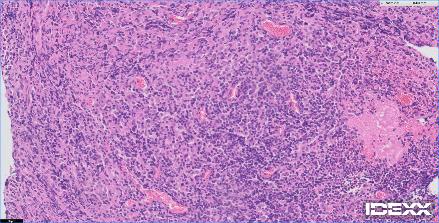

12歳の猫が2週間前よりふらつき、食欲不振、硬直性の痙攣があるとのことで、主治医から紹介がありました。MRIでは前頭葉を中心としたMASSエフェクトを伴う病変が確認されました。リンパ腫あるいは髄膜腫が強く疑われました。CSFでは無色透明で髄液蛋白60mg/dl、Ph8.5 細胞数2(5以下正常)単核球100%パンディ反応(+1)。CSF中のGlu63mg/dl、CK<10、Na 166 K 2.9 Cl 131。手術までの1週間の間にステロイドを中心とした内科療法を実施したところ、臨床症状も改善し、再度、実施したMRIでも以前の病変がほぼ消失していました。ステロイドに強く反応したことからリンパ腫の存在が強く疑われました。今後、化学療法を継続するか?否か?あるいはFIPなどの鑑別を行うために、嗅球と前頭葉の生検が行われました。生検の結果、コロナウイルスの感染、リンパ腫の存在は否定されました。また、血清学的にもトキソプラズマ、FIPの関与は否定的でした。そのため、プレドニゾロンを継続し、経過観察中です。2017年に猫のMUOについて世界で初めてイギリスより16例のまとまった報告が初めての論文として掲載されており、今回の患者さんはそのFMUOのカテゴリーに分類されると考えられました。